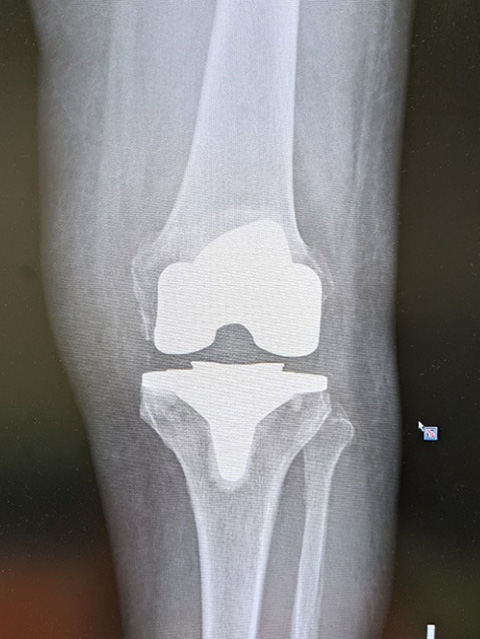

人工膝関節全置換術 (TKA)

• 人工膝関節全置換術 (TKA)

傷んだ膝関節の骨、軟骨を切除して、大腿骨側、脛骨側にそれぞれ人工関節を挿入し関節の機能を再建する手術です。骨を切る際に、骨を切る量を調節してO脚やX脚を矯正します。